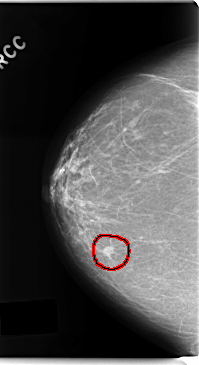

C_0192_1.RIGHT_CC

RIGHT_CC LINES 4744 PIXELS_PER_LINE 2584 BITS_PER_PIXEL 12 RESOLUTION 50 OVERLAY

FILE: C_0192_1.RIGHT_CC.OVERLAY

TOTAL_ABNORMALITIES 1

ABNORMALITY 1

LESION_TYPE MASS SHAPE OVAL MARGINS SPICULATED

ASSESSMENT 5

SUBTLETY 5

PATHOLOGY MALIGNANT

TOTAL_OUTLINES 1

BOUNDARY